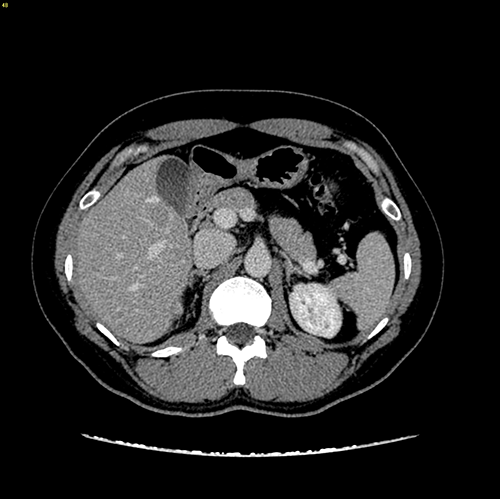

S5 肝癌--腹腔镜S5切除